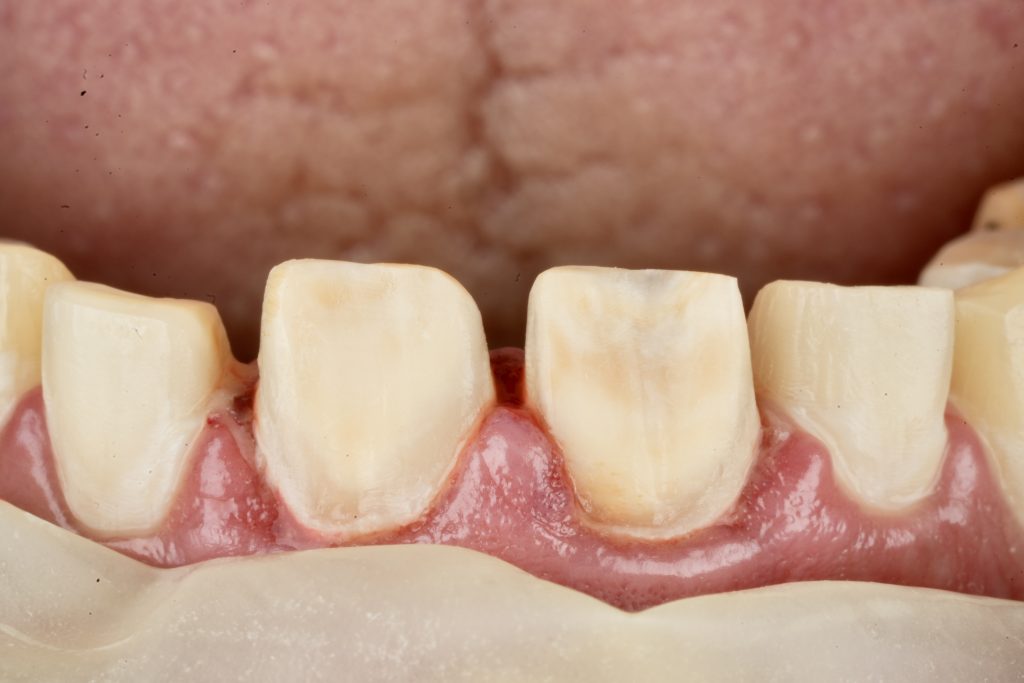

2️⃣ Guided Tooth Reduction

Using silicone indexes derived from the mock-up, controlled minimal-thickness veneer preparations (0.3–0.5 mm) were carried out under microscope magnification to ensure uniform reduction and margin clarity (Fig 2). Finish lines were placed juxta-gingivally with soft-tissue protection using Teflon and double-cord isolation.